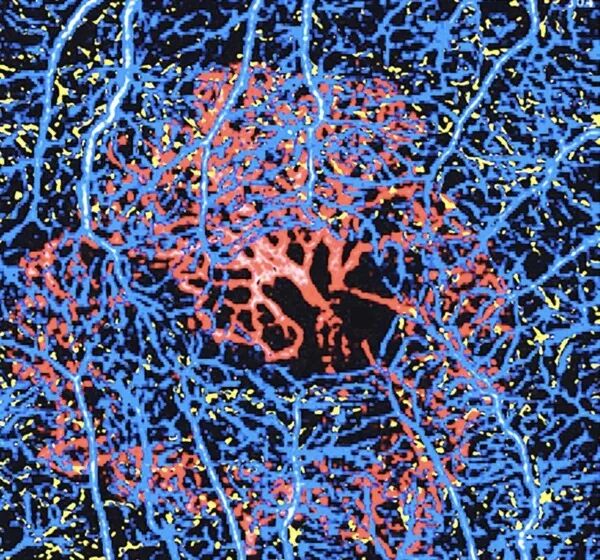

OCT-Angiography, or OCTA, is an angiography technique combined with optical coherence tomography (OCT), and it does not require any contrast agent injection. This relatively recent technology has enabled the discovery of new pathologies and the early detection of subclinical macular disorders